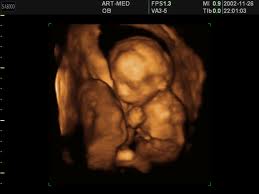

Термин «ультразвук» относится к звуковым волнам сверхвысокой частоты, используемым в диагностических целях. Эти волны распространяются со скоростью от 10 до 20 миллионов циклов в секунду, в отличие от 10 до 20 тысяч циклов в секунду для слышимого звука. Ультразвуковые волны излучаются передатчиком (та часть аппаратуры, которая прикладывается к телу), и из рисунка отраженных «эхо»-волн выстраивается картинка нижележащих тканей. Твердые поверхности, такие как кость, отражают более сильное эхо, чем мягкие ткани или жидкости, придавая костяному скелету белый цвет на экране.

В обычных аппаратах УЗИ используются импульсы ультразвука, длящиеся только долю секунды, а во время интервала между волнами аппаратура распознает отраженное эхо. В противоположность этому, техника допплера, используемая для специальных обследований, фетальных мониторов и ручных фетальных стетоскопов излучает продолжительные волны, давая значительно больший уровень воздействия, чем «пульсовый» ультразвук. Многие женщины не осознают, что маленькие аппараты для прослушивания сердечного ритма их младенцев на самом деле используют допплер-ультразвук, хотя бы и низкого уровня воздействия.

В последние годы ультрасонографисты стали использовать вагинальное ультразвуковое исследование, при котором передатчик помещается высоко во влагалище, намного ближе к развивающемуся телу. Этот метод используется преимущественно на ранних сроках беременности, когда сканирование через стенку брюшины не может дать качественного изображения. Однако, во время вагинального УЗИ уровень воздействия будет высоким, т.к. пока еще нет достаточного количества промежуточной ткани, защищающей младенца, находящегося на уязвимой стадии развития. Вагинальное УЗИ не является приятной для женщины процедурой. Термин «диагностическое изнасилование» был введен в практику в целях описания тех чувств, которые испытывают некоторые женщины во время вагинального обследования.